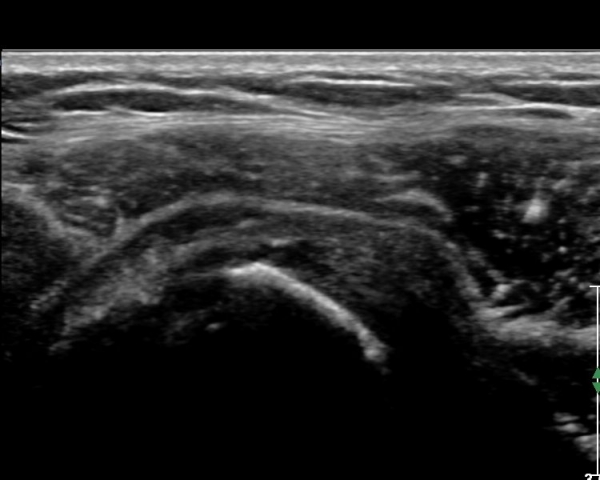

Å½ÃËÀÚ¸¦ Á»´õ ¸»´ÜÀ¸·Î À̵¿ ÈÄ(¶Ç´Â ¾Æ·¡·Î ±â¿ïÀÎ ÈÄ) ³»ÃøºÎ¸¦ Á¶ÀýÇÏ´Ï °ß°©ÇϱٰÇ

Ç¥ÃþÀ¸·Î Á¡¾×³¶³» ¼ö¾×Àú·ù°¡ °üÂûµÈ´Ù(»çÁö 3, 4). ŽÃËÀÚ¸¦ Á¶Á¤ÇÏ´Ï ÀÌµÎ¹Ú°Ç ÁÖÀ§ ¼ö¾× Àú·ù¿Í